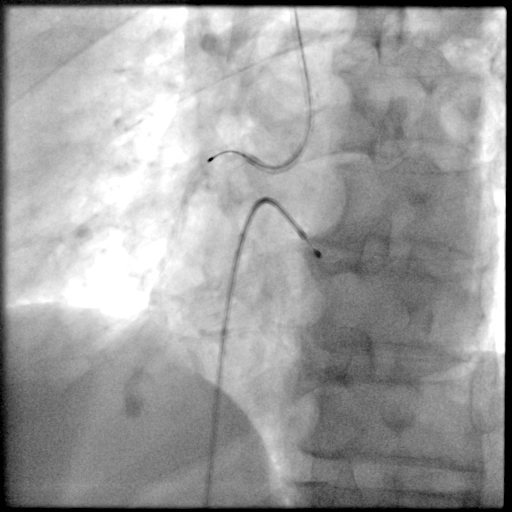

PCI过程-球囊PTCA

预置临时起搏器后,7F AL1.0无法到位,更换为7F SAL1.0至RCA开口,应用非顺应性球囊2.5X15mm,于RCA中段病变处以12-18atm扩张,球囊膨胀不佳。

PCI过程-冠状动脉旋切(轨道旋磨)术-1

IVUS导管无法通过,微导管辅助下,将旋磨导丝置于RCA远端,应用1.0mm磨头以13万转反复旋磨钙化病变处(每次15秒,磨头推进速度不超过10 mm/s)